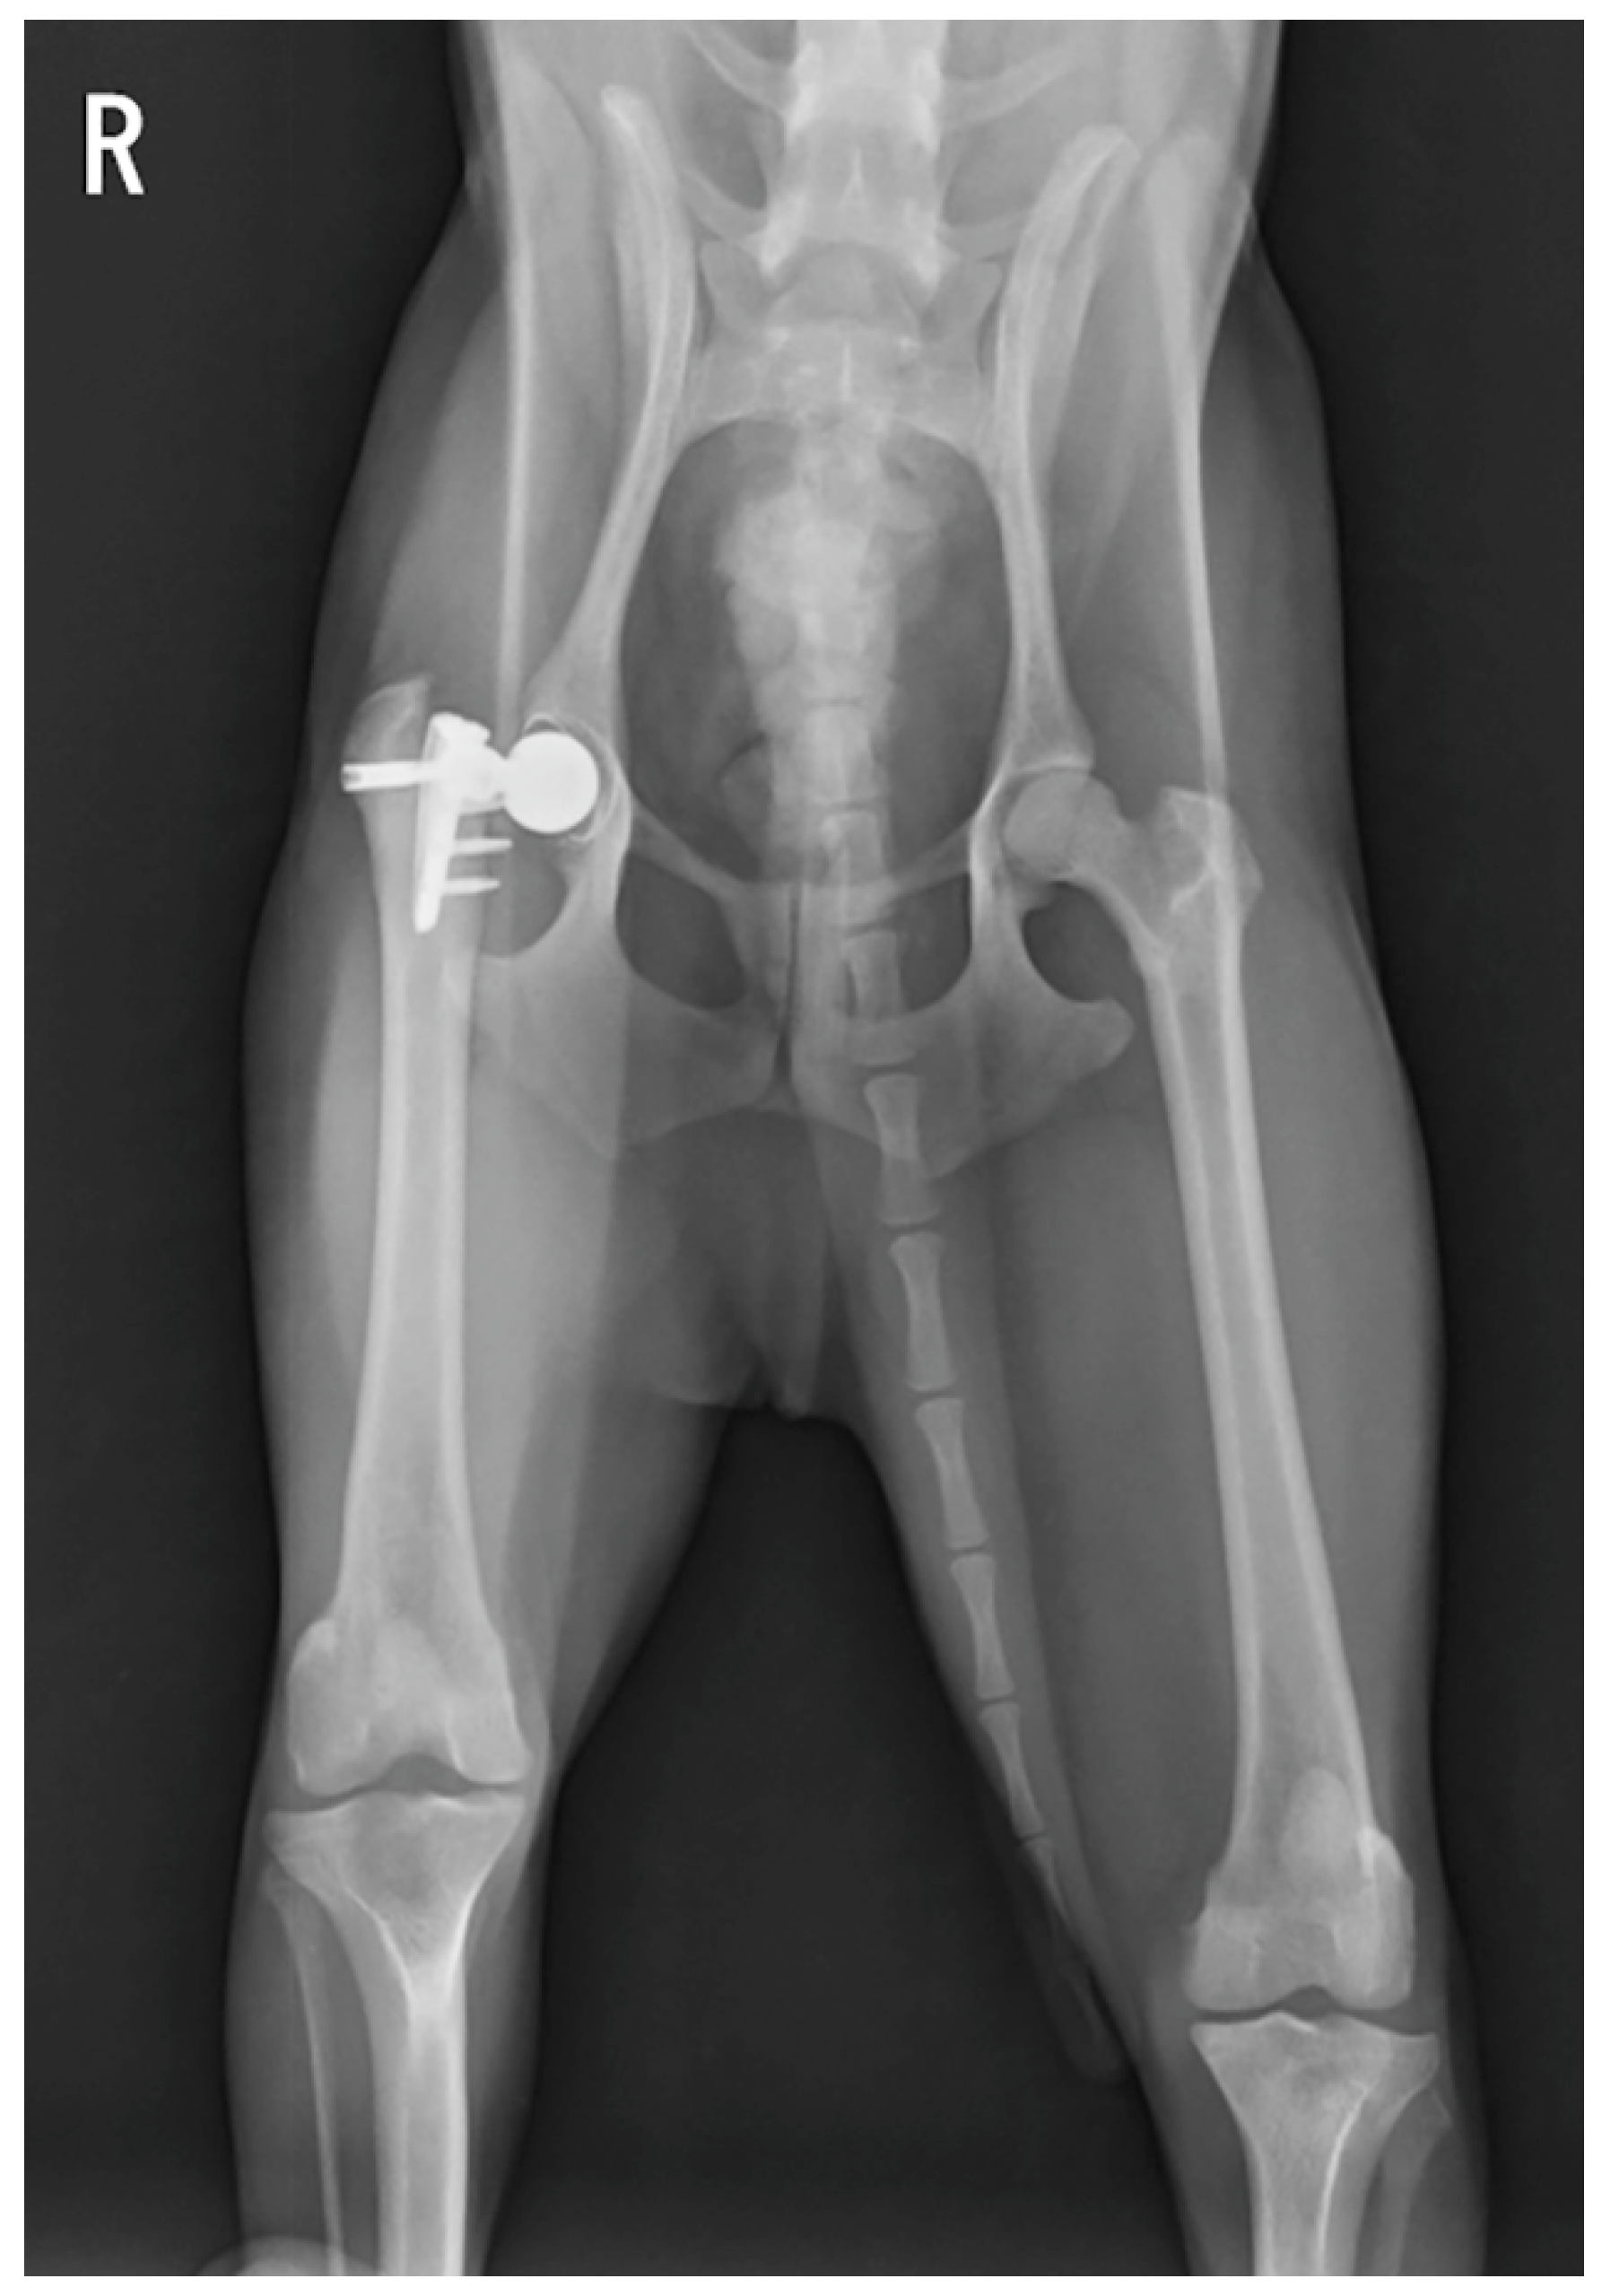

Figure 2.

Ventrodorsal radiograph of the dog 176 days after the first surgery. This radiograph shows that the femoral stem fractured at the peg.